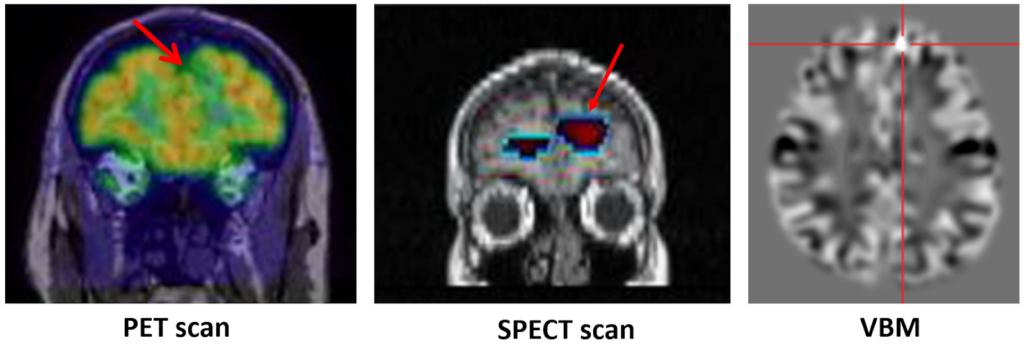

⦁ ผู้ป่วยที่ไม่มีสาเหตุจำเพาะ แต่ไม่ตอบสนองต่อการรักษาด้วยยากันชัก 2 ชนิดขึ้นไป และอาการชักมีผลเสียต่อคุณภาพชีวิตของผู้ป่วย ซึ่งในปัจจุบัน ผู้ป่วยในกลุ่มนี้ แม้ว่าจะไม่มีรอยโรคจากการตรวจ MRI หรือ มีคลื่นชักกระจายหลายตำแหน่งในสมอง ซึ่งในสมัยก่อนอาจจะผ่าตัดไม่ได้ แต่ด้วยวิวัฒนาการการผ่าตัดได้ก้าวหน้าไปมาก มีเทคนิคการตรวจทางห้องปฎิบัติการหลายอย่างเพื่อสามารถหาตำแหน่งกำเนิดชัก ไม่ว่าจะเป็นการตรวจการไหลเวียนของเลือดไปที่สมองด้วยสารไอโซโทป (SPECT scan) การตรวจหน้าที่สมองด้วย positron emission tomography (PET Scan), การตรวจภาพคลื่นแม่เหล็กไฟฟ้าแบบ 3 มิติ (voxel-based morphometric: VBM) เป็นต้น (ดังรูปที่ 2)

รูปที่ 2 การตรวจหาจุดกำเนิดชักด้วยวิธีต่างๆ